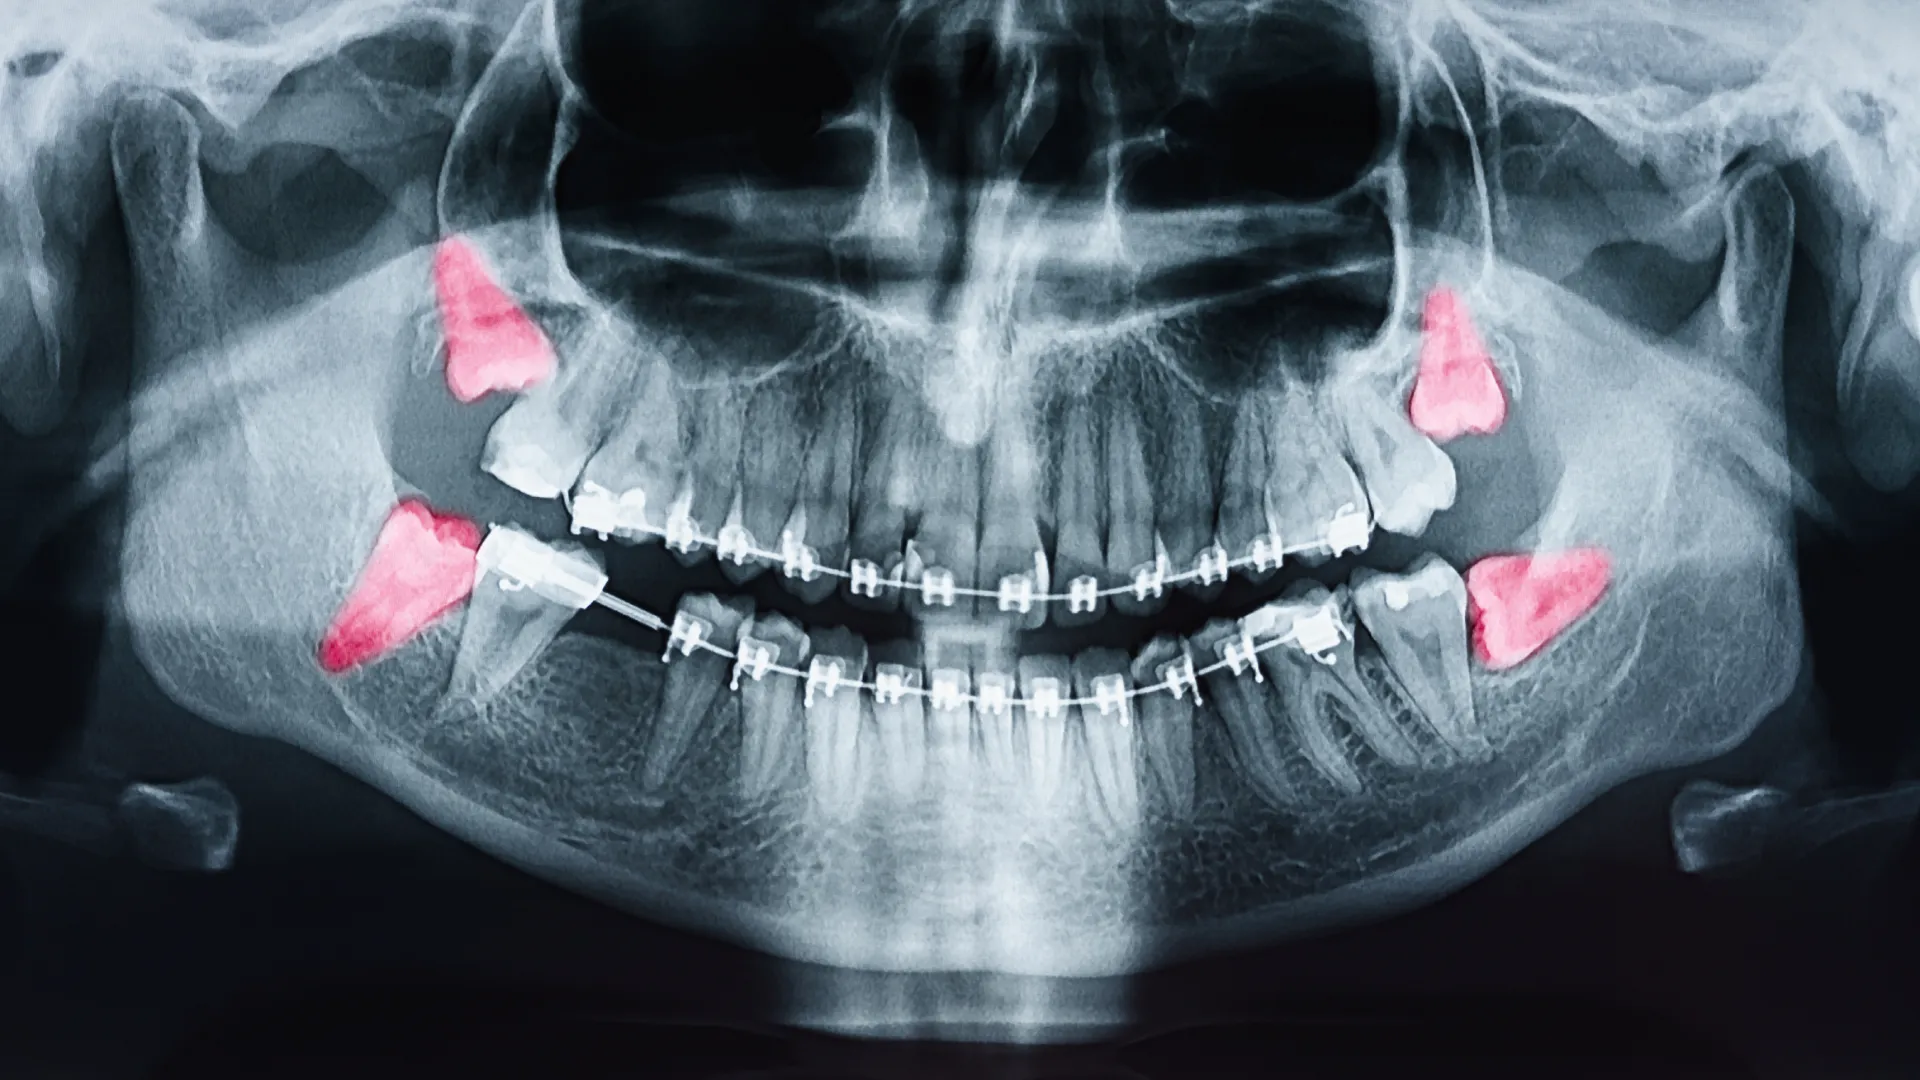

Most adults naturally have 4 wisdom teeth, but about 15-20% of people never develop at least one of these four teeth. What are called wisdom teeth are the third and last molars, which are found at the very bottom on each side of the upper and lower jaws. They are the last teeth to grow through the gums – hence their name wisdom teeth. Wisdom teeth often develop without posing any particular problem. However, sometimes the wisdom tooth does not have enough space to grow and causes severe pain.